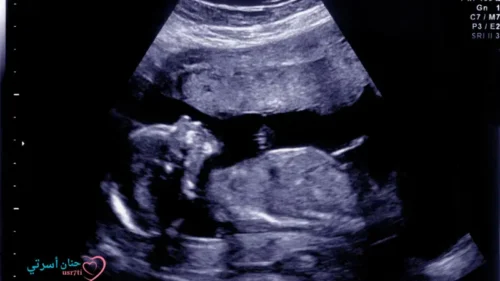

هل تساءلت يوماً عما إذا كان جنينك يحصل على التغذية الكافية في الأسابيع الأخيرة من الحمل؟ إن الشهر التاسع من الحمل يُعتبر من أهم المراحل في رحلة نمو الطفل، حيث يكتسب الجنين معظم وزنه خلال هذه الفترة الحاسمة. كأم حامل، تريدين التأكد من أن طفلك ينمو بشكل صحي ويصل إلى الوزن المثالي قبل الولادة.

يُعد وزن الجنين في الشهر التاسع مهماً، إذ يمر الجنين بمرحلة نمو مكثفة ويكتسب حوالي 200-300 جرام أسبوعياً. هذه الزيادة في الوزن ليست مجرد أرقام، بل تعكس نضج الأعضاء الحيوية واستعداد الطفل للحياة خارج الرحم . تشكل الأطعمة التي تزيد وزن الجنين في الشهر التاسع دوراً حاسماً لضمان توفير العناصر الغذائية الأساسية لنمو الطفل السليم.